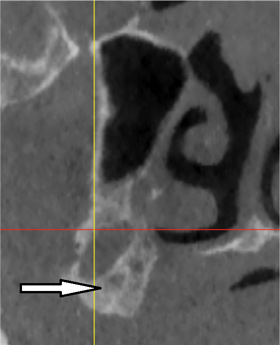

Fig 3. Submandibular fossa and mylohyoid ridge: cross-sectional view. A: The submandibular fossa may present a large depression in the mandible. B: The mylohyoid ridge provides the origin for the mylohyoid muscle.

Figure 3